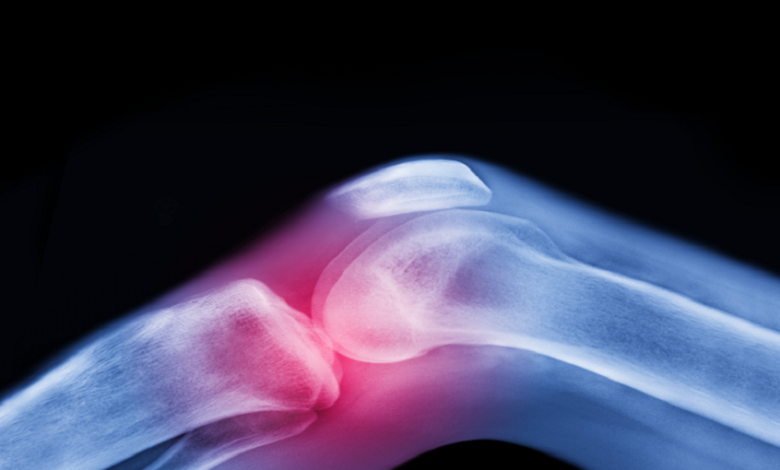

علاج لمرض السكري يساعد في تخفيف آلام الركبة

أجرى فريق من الباحثين في جامعة موناش، دراسة جديدة استهدفت تأثير أحد الأدوية الشائعة في علاج مرض السكري على الأشخاص الذين يعانون، التهاب مفاصل الركبة وزيادة الوزن أو السمنة.

وأظهرت الدراسة، أن الميتفورمين، المستخدم عادة لعلاج السكري من النوع الثاني، يمكن أن يساعد في تخفيف آلام الركبة الناتجة عن هشاشة العظام لدى الأشخاص الذين يعانون زيادة الوزن أو السمنة، ما قد يؤخر الحاجة إلى عمليات استبدال الركبة.

ووجدت الدراسة، أن المرضى الذين تناولوا الميتفورمين أبلغوا عن انخفاض في شدة الألم بمقدار 31.3 نقطة على مقياس من 0 إلى 100، مقارنة بـ 18.9 نقطة فقط لدى المجموعة التي تناولت الدواء الوهمي. وأشارت النتائج إلى أن الميتفورمين يمكن أن يكون علاجاً فعالاً في تخفيف آلام الركبة المصاحبة لهشاشة العظام.